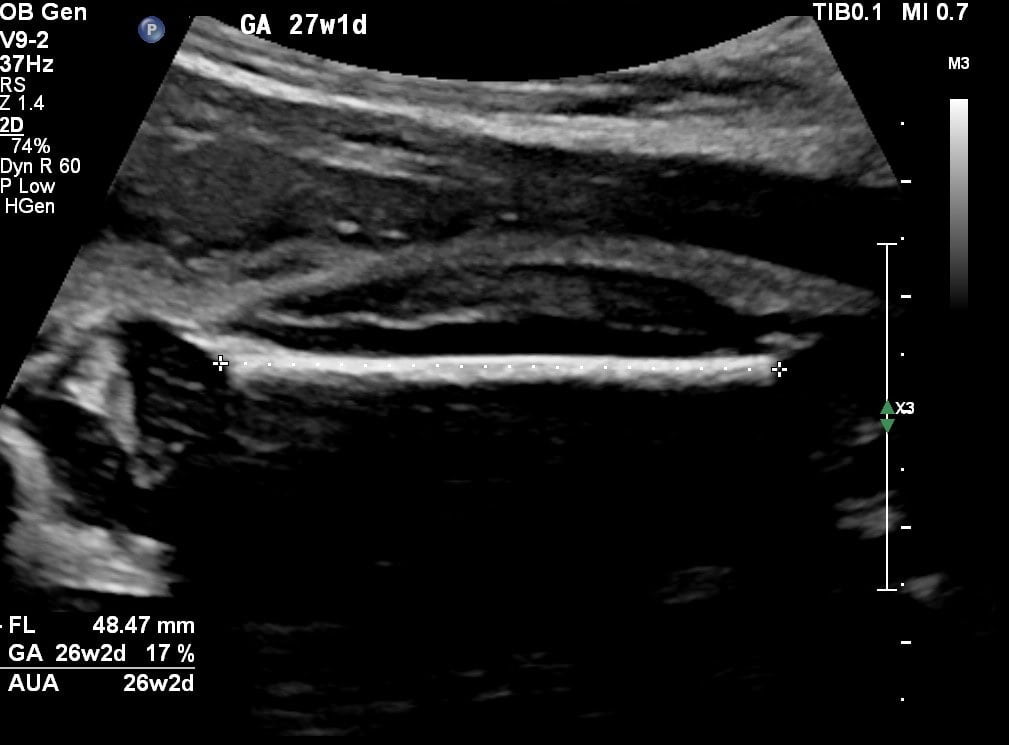

If your uterus is growing well, the baby is also growing well. Are you completely healthy yourself and your baby is growing well? Then no growth ultrasound is necessary. If you have an increased risk of a small or large baby, the midwife will agree with you to do a growth ultrasound. This is also done when the baby’s growth cannot be felt well through the abdomen. During a growth ultrasound, the baby’s head, abdominal size and upper leg are measured and the amount of amniotic fluid is determined. It often takes several ultrasounds to know if the baby is growing as expected.